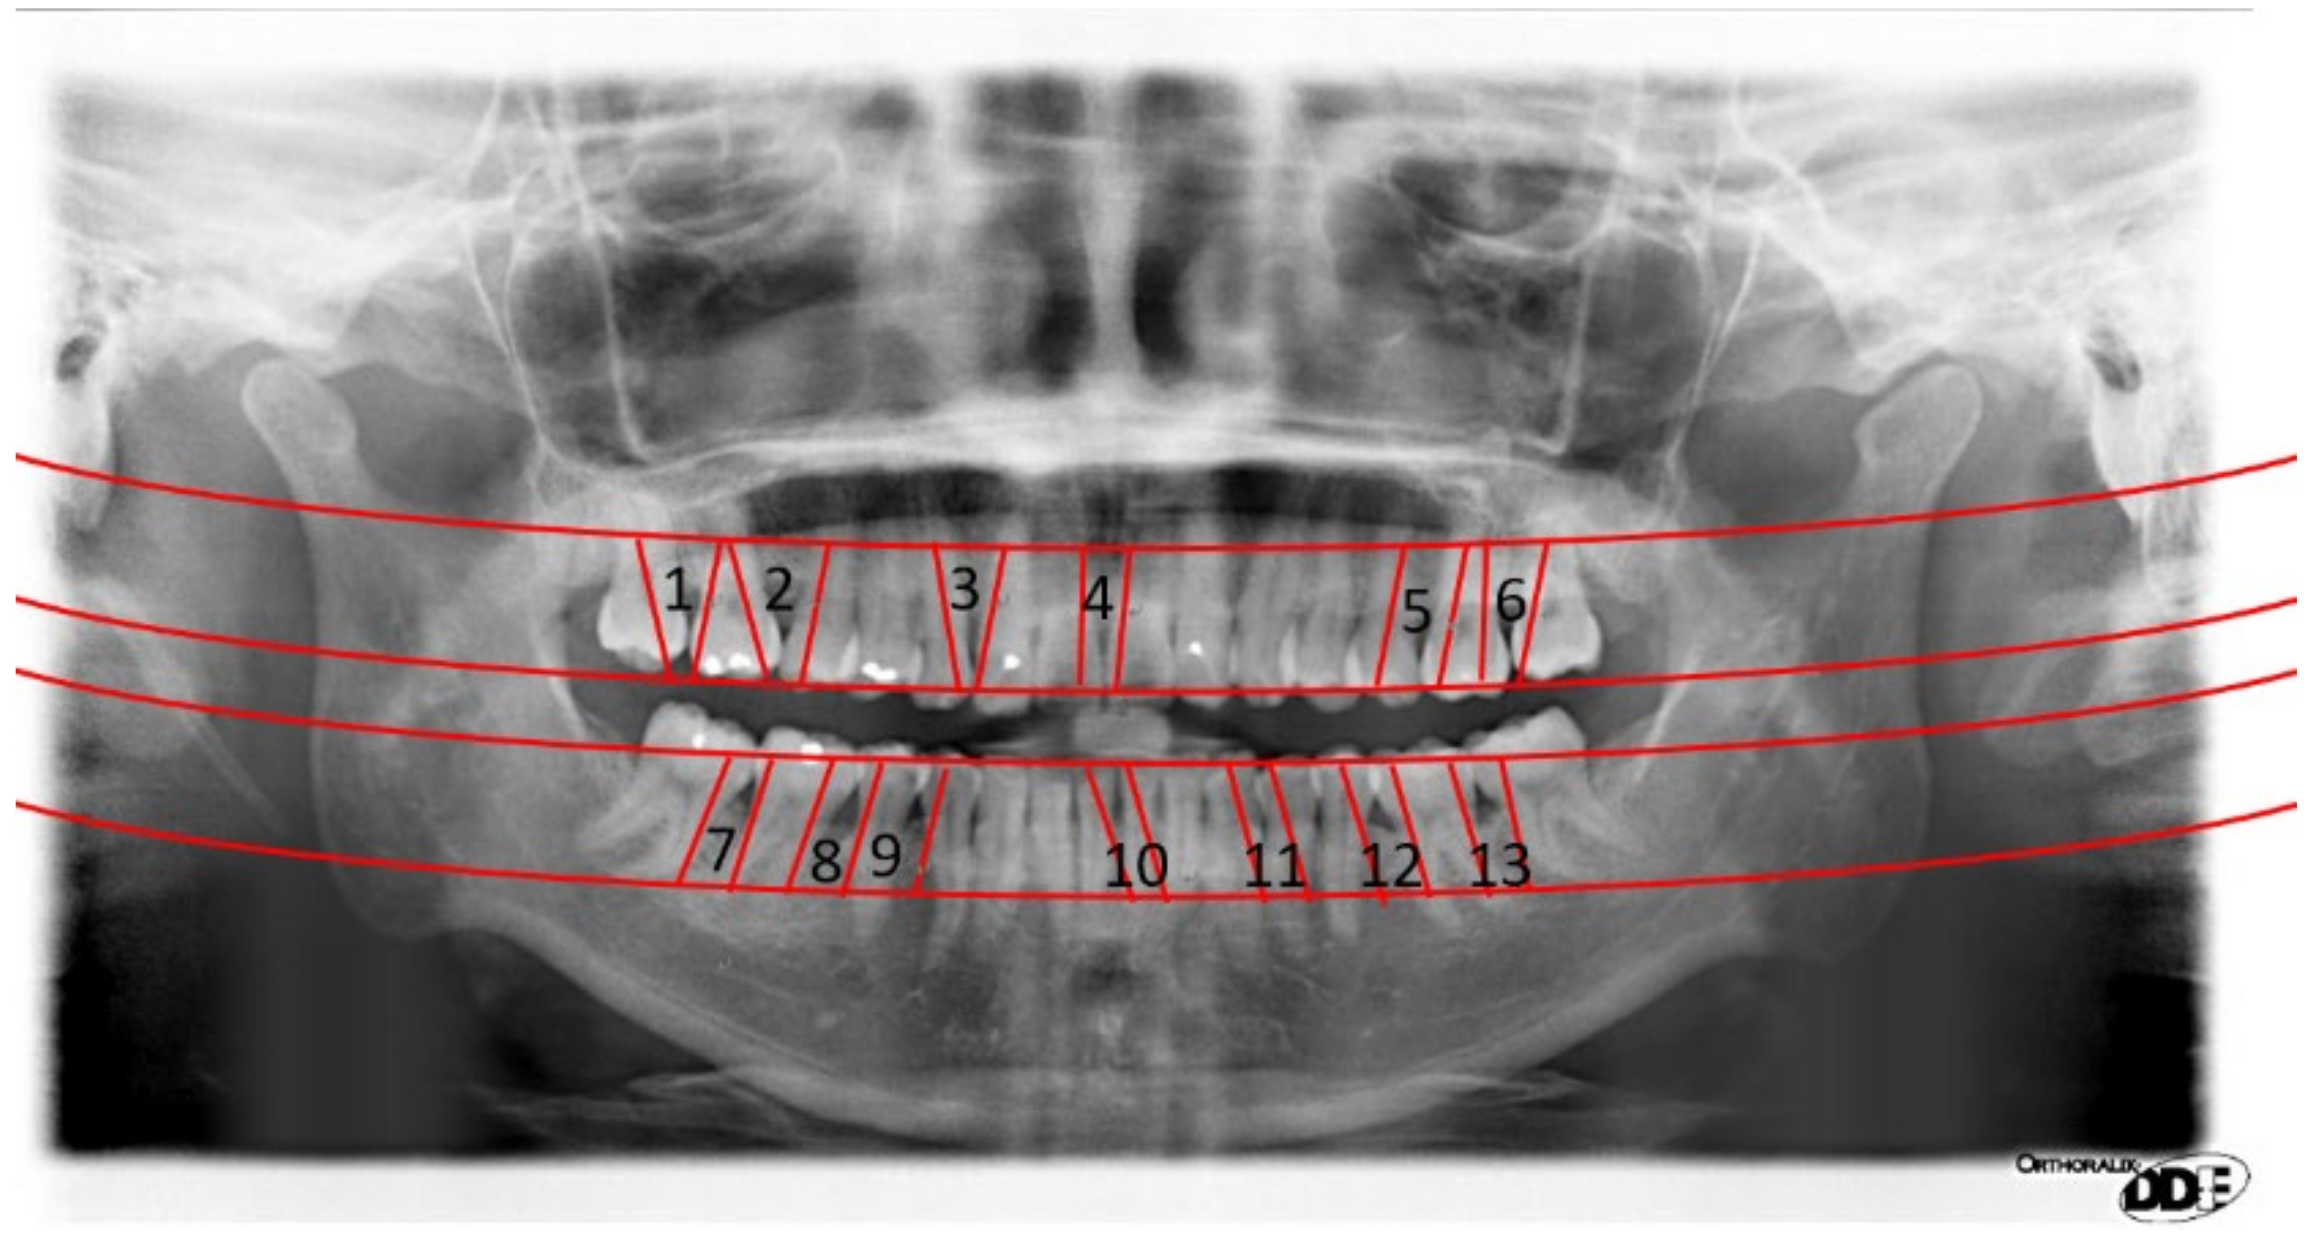

2.2.1. Curve of the Mouth

2.2.2. Curve Adjustment

2.2.3. Positioning Numbers